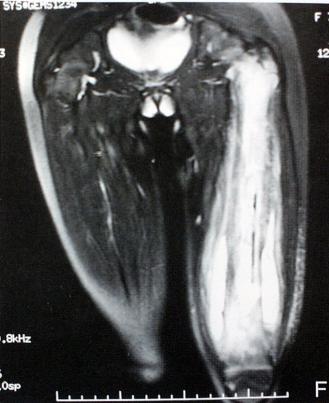

3.临床表现:1、外伤史,2、肿胀、疼痛、髋关节活动受限,后脱位:患者缩短;髋关节屈曲、内收、内旋(弹性固定),黏膝征(+),前脱位:患肢增长;髋关节屈曲、外展、外旋(弹性固定),黏膝征(-),中心性脱位:股骨头严重移位者,大粗隆内移,患肢短缩。

2.脱位分型:以髂坐线(Nelaton:坐骨结节至髂前上棘的连线。正常情况下,此线经过大转子尖端,当股骨颈骨折或髋关节后脱位时,大转子尖端可向上移位超过此线。)为标准:前方——前脱位(外展位);后方——后脱位(内收位);中心脱位:股骨头突破髋臼底部或入盆腔(合并有髋臼横行骨折,或髋臼顶骨折或者髋臼复杂性骨折,并入髋臼骨折处理)

1.脱位原因:高能量损伤才能脱位,车祸、高坠伤等,发生率约占全身各关节脱位的5%,85%-90%为后脱位,多发生于青壮年

髋关节脱位(股骨和骨盆髋臼之间的关节失去了正常位置)